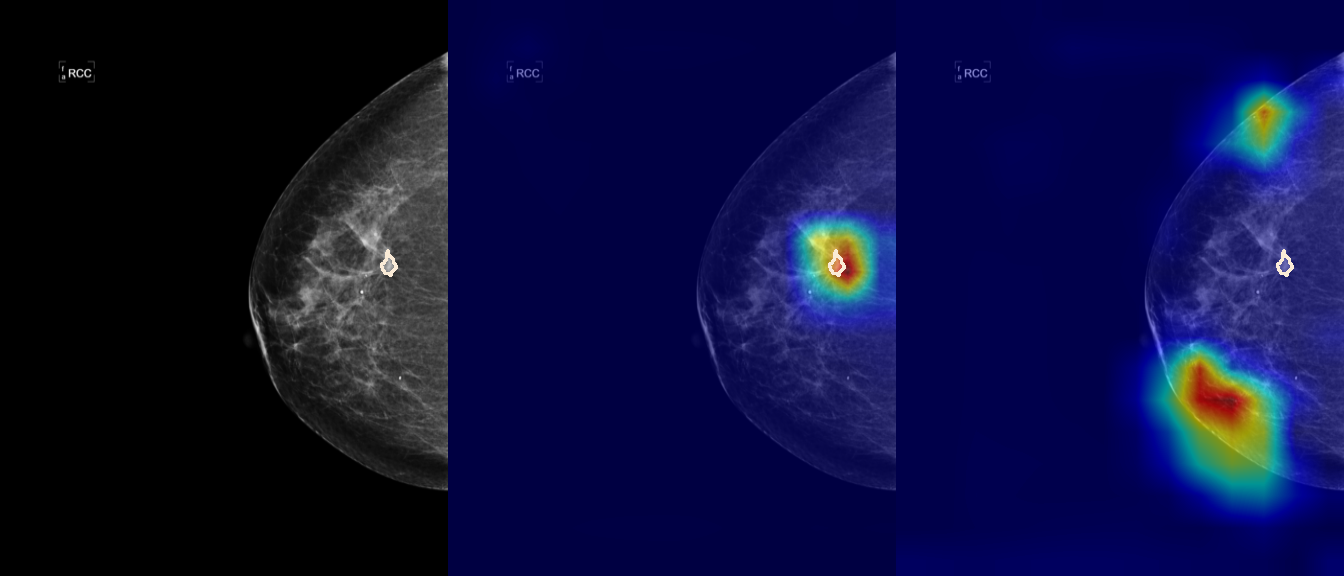

To interpret the decision-making process behind the quantitative results, we visualized Class Activation Maps (CAM) for the top-performing methods, ERM and VREx. Figures 1 through 2 illustrate discriminative regions identified by the models within the full mammograms.

Localization of Clinical Features: A key concern in medical AI is whether high performance stems from genuine pathology detection or spurious background correlations. Our visualizations suggest that Standard ERM achieves its superior quantitative performance by predominantly prioritizing clinical cues. As shown in the top rows of the Figure 1 and Figure 2, the ERM-trained models consistently focus attention on the specific lesion regions within the breast tissue. This demonstrates that despite lacking explicit invariance constraints, ERM is capable of learning robust, medically relevant features when trained on diverse multi-source data.

Attention Drift in Both Methods: While both ERM and VREx generally identify the correct region of interest in successful cases, neither method is immune to attention drift. We observe instances in both training paradigms where the model focuses on irrelevant areas, such as healthy fibroglandular tissue or background artifacts (e.g., rows 5 and 6 in Figure 1). This indicates that while VREx is designed to penalize instability, it does not guarantee perfect anatomical focus compared to the unconstrained ERM baseline.